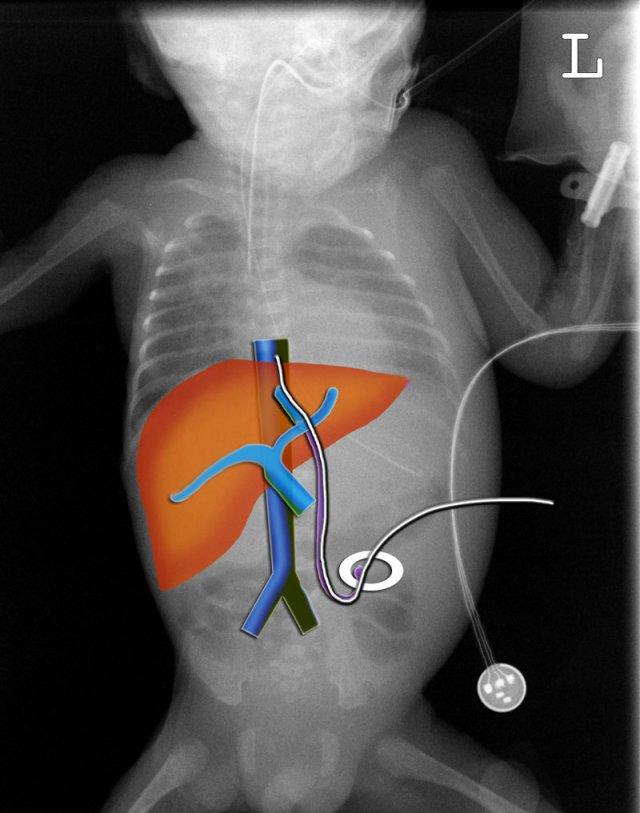

Các phát hiện bao gồm:

- Đường truyền tĩnh mạch rốn được đặt ở ngoại vi gan qua tĩnh mạch cửa phải.

- Đường truyền động mạch nằm trong động mạch dưới đòn trái.

Đường truyền tĩnh mạch rốn (3)

Hãy quan sát kỹ hình ảnh trước.

Sau đó tiếp tục đọc.

- Đây là phim chụp X-quang tư thế nằm nghiêng với chùm tia ngang.

Hình ảnh minh họa đường truyền tĩnh mạch rốn đi theo đường đi của tĩnh mạch rốn vào trong gan (mũi tên xanh).

Đường truyền chưa đủ sâu. - Đường truyền động mạch rốn đầu tiên đi xuống phía dưới và vào động mạch chậu (mũi tên đỏ).